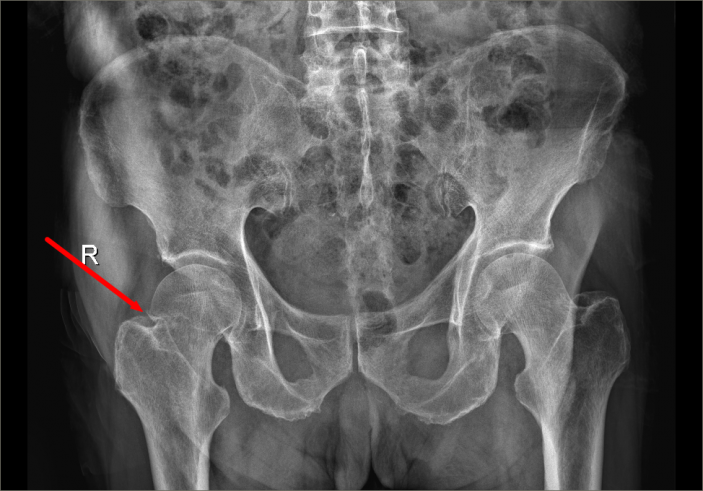

近日,骨科又收治了一位98歲高齡來自占隴鎮的股骨頸骨折患者,該名患者合并有高血壓、糖尿病、肺部感染、泌尿系感染、心律失常、後循環缺血等基礎疾病和并發症,手術治療非常棘手。